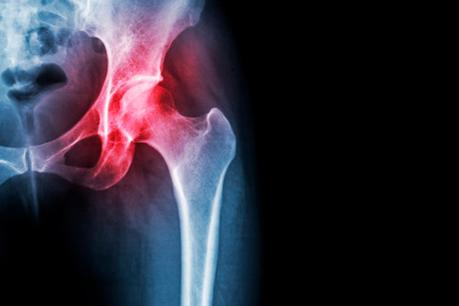

La artrosis afecta con más frecuencia a ciertas articulaciones, como son las rodillas, las vértebras y las caderas porque son las articulaciones que funcionan como puntos de apoyo sobre las que reposa el cuerpo.

Síntoma habitual de la artrosis de cadera es el dolor en el pliegue de la ingle, puede descender por la pierna y llegar hasta la rodilla. Caminar y los movimientos de rotación duelen, por ejemplo, se sufren molestias al colocarse los calcetines.